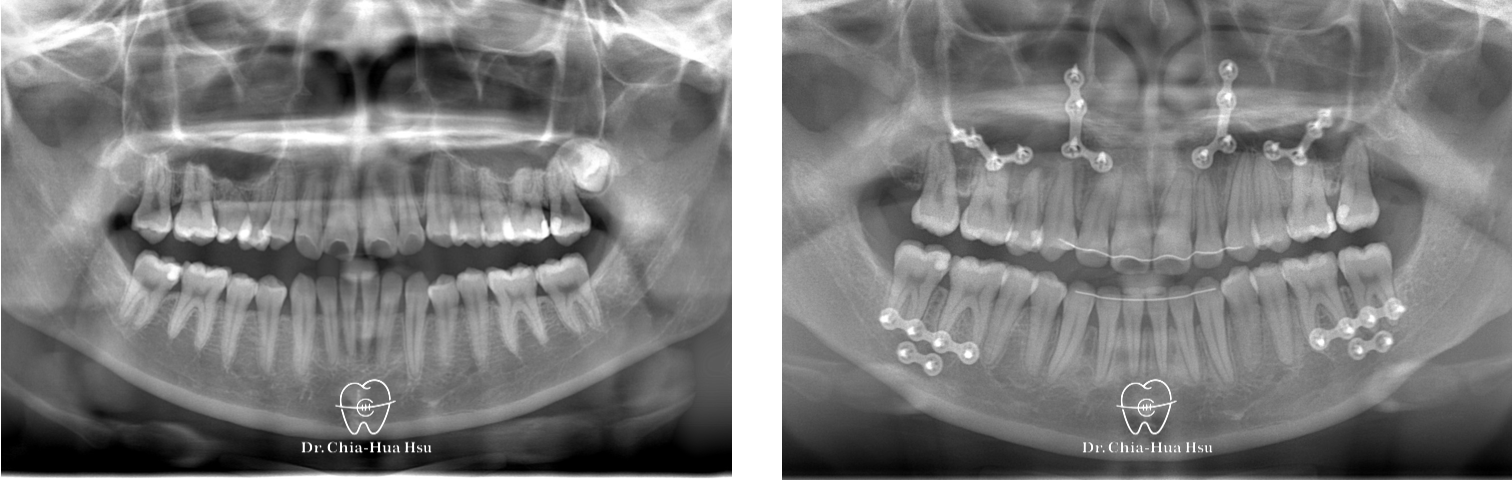

• 20多歲的日籍大學生小時候有做過矯正治療,不過下顎骨隨著年紀持續生長,變成戽斗且開咬的樣子。於是,患者接受了矯正合併正顎手術,不但改善外觀,也改善了咬合功能與牙齒排列(患者很開心可以咬斷麵條)。

• 病患主訴:戽斗、前牙開咬。

• 問題分析:患者是標準的骨骼三類咬合(Skeletal Class III),下巴明顯較長,還有上顎牙弓過窄、開咬以及齒列不正。

• 治療方式:使用傳統金屬矯正器,合併正顎手術(雙顎),上顎拔除兩顆小臼齒以利手術方式進行上顎牙弓擴寬。

• 治療時間:1 年 7 個月。

• 治療結果:齒列排齊,咬合功能恢復,外觀更和諧。